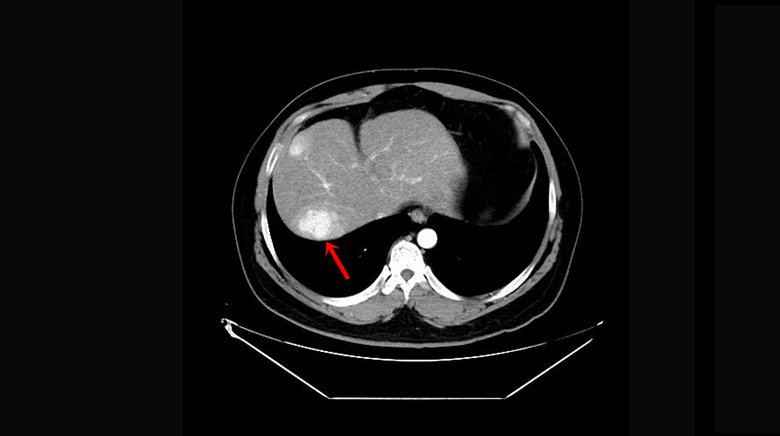

亞大醫院一般外科主治醫師王銘嶼指出腫瘤位置。(圖/亞洲大學附屬醫院提供)(圖/轉載自NOW健康)

亞洲大學附屬醫院一般外科主治醫師王銘嶼表示,張先生的肝硬化程度嚴重,執行手術風險過高,故先採取栓塞化學治療,透過切斷腫瘤的氧氣和營養供應,同時讓化療藥物殺死肝癌細胞,再以手術切除肝臟第四葉和第七葉,但肝臟第四葉因左右有供應血管,且上方有大型肝靜脈,手術困難度高,考量患者肝功能不佳,故改以執行「肝臟兩處切除手術」,盡可能保留其肝功能,術後2周患者順利出院。